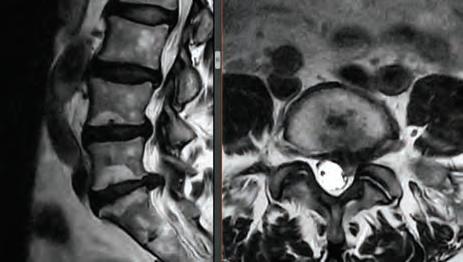

Stephen P. Courtney, MD ORTHOPEDIC SPINE SURGEON

Stephen P. Courtney, MD

Fellowship-Trained Orthopedic Spine Surgeon

Over 26 Years of Experience

Dr. Courtney is a board-certified orthopedic spine surgeon located in Plano, Texas. A Louisiana native, he attended Louisiana State University for medical school, and completed residency at Texas A&M followed by a fellowship at the Florida Neck and Back Institute.

BOARD-CERTIFIED, FELLOWSHIP-TRAINED ORTHOPEDIC SPINE SURGEON PRACTICING FOR OVER 28 YEARS.

For board-certifid, fellowship trained orthopedic spine surgeon

Dr. Stephen P. Courtney, patients come fist. It’s an ethos that developed early on in his life and one that has helped guide him in his journey to earn a distinguished reputation among his professional colleagues, medical peers and, most importantly, his patients.